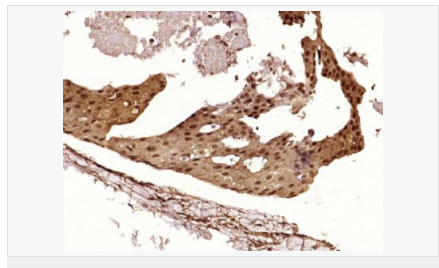

| 產(chǎn)品應(yīng)用 | WB=1:500-2000 ELISA=1:5000-10000 IHC-P=1:100-500 IHC-F=1:100-500 Flow-Cyt=1μg/Test ICC=1:100 IF=1:100-500 (石蠟切片需做抗原修復(fù)) not yet tested in other applications. optimal dilutions/concentrations should be determined by the end user. |

| 細胞定位 | 細胞核 細胞漿 |